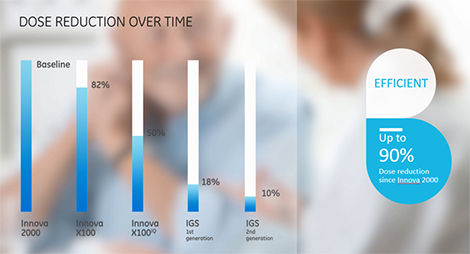

As an interventionalist, you want to diagnose and treat all your patients, even the most challenging ones, safely and efficiently, with the best possible image quality. Designed for cardiac and peripheral procedures, the OptimaTMIGS 330 is based on proven technology and very efficient imaging chain, providing superior image quality at lowest possible dose.

It includes features like Dose Personalization, which gives you the tools to choose from up to four automatic exposure preferences for your system. You can also modify any of these preferences1in any clinical protocol to enable multi-procedure, m ulti-user customization and thus support well-informed decisions.Powered with a comprehensive set of advanced interventional imaging software, you can expand your clinical versatility and successfully plan, guide and assess increasingly sophisticated procedures with greater precision and dose efficiency.